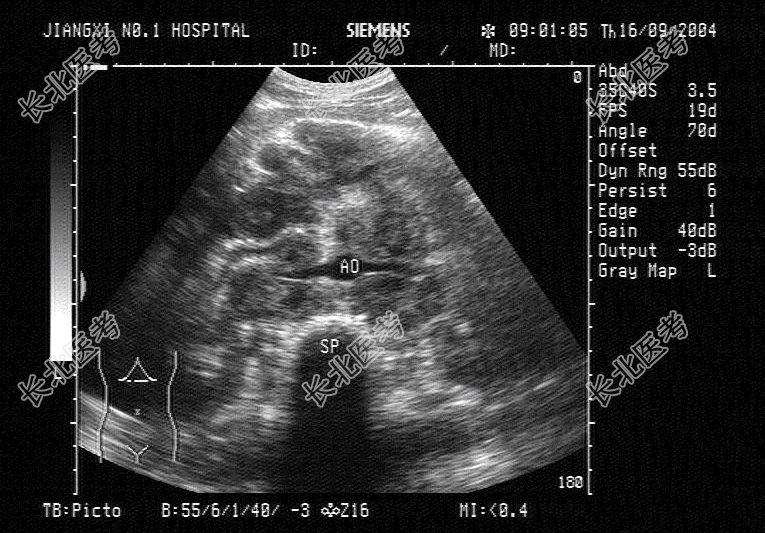

- 单项选择题患者,低热, 清洁灌肠后,中腹部超声声像图可见融合成团的异常光团, 超声检查如图,最有可能诊断为

A、胰腺癌

B、淋巴瘤

C、结肠癌

D、腹腔结核

E、腹膜后肿瘤